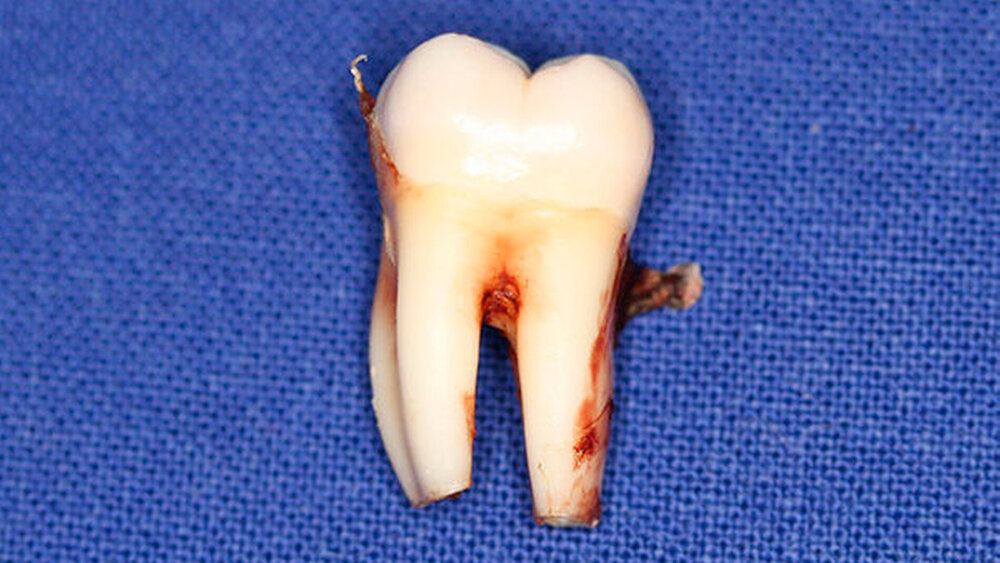

Postoperativ wurden die Zähne in bukko-lingualer Richtung mittels einer diamantbelegten Trennscheibe geteilt. Visuell zeigte sich nun ein großer Hohlraum im koronalen Dentinbereich, sowohl an Zahn 27 als auch an Zahn 47. Die histologische Untersuchung der Zahnfragmente ergab für beide Zähne: Zahnanlagengewebe mit akuter Entzündung (Abbildungen 4 bis 6). Der Patient befindet sich seitdem im regelmäßigen Abstand von sechs Monaten in einem prophylaktischen Recall. Die Abbildung 7 zeigt das postoperative Zahnschema vom 19. August 2015

Der vorliegende Fall zeigt eindrucksvoll verschiedene Stadien der präeruptiven koronalen Resorption (PIR): eine präeruptiv im Röntgenbild sichtbare Transluzenzzone im Dentin des Zahns 47 an der koronalen Schmelz-Dentin Grenze mit intaktem Schmelzmantel und eine große Kavitätenbildung nach Durchbruch des Zahns 27 in die Mundhöhle.

Bei der histologischen Untersuchung der extrahierten Zähne 27 und 47 unseres Patienten wurden Zahnanlagengewebe und Entzündungszellen gefunden. Im Rahmen anderer Untersuchungen konnten resorptive Zellen wie Osteoklasten und Makrophagen an den Rändern der Läsion nachgewiesen werden [Spierer, 2014].